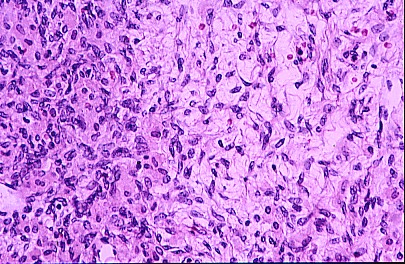

Figura 5

La Figura 5 muestra parte de un Cuerpo luteo y severo edema del estroma H y E X40.